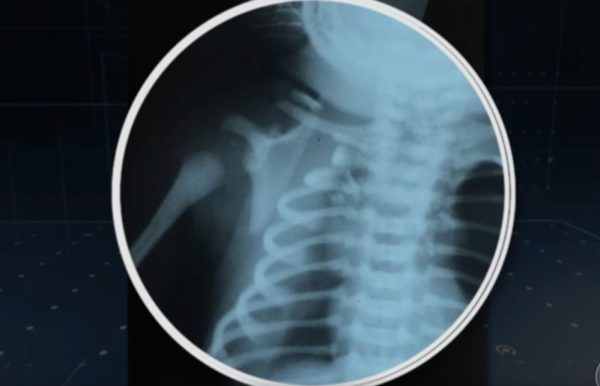

Ele foi baleado no peito e sofreu uma pneumotórax bilateral (entrada de ar dentro da pleura, a membrana que recobre os pulmões). A bala entrou pelo ombro direito e atravessou o tórax. Nos seus primeiros minutos de vida, os médicos precisaram drenar o ar para voltar a expandir o pulmão de Arthur.